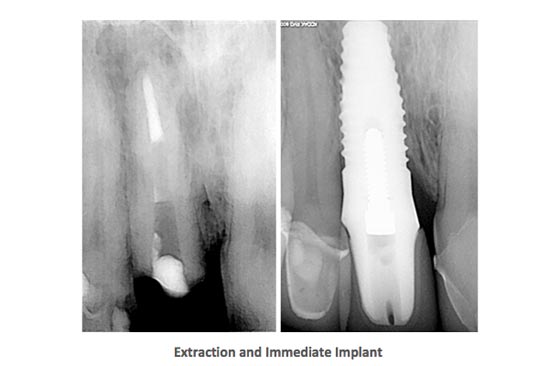

Dental Implant Cases

Dental Implants Case StudyDental Implants Case StudyDental Implants Case Study